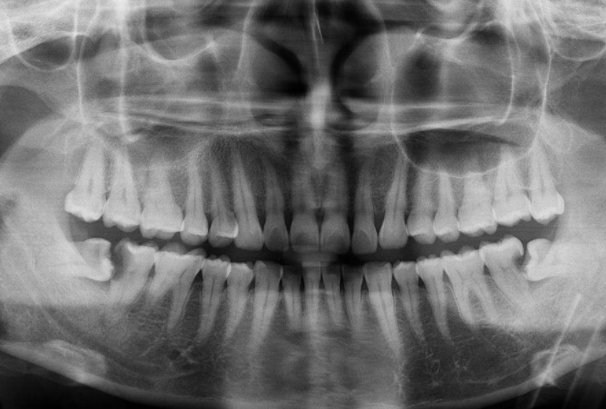

通常遇见阻生智齿的话一般都是去医院将它拔出来,不过如果智齿长得很好的话,那么就不会出现任何发炎或其他的问题,因此就不需要管它,但是有些人的智齿会出现各种各样阻生智齿的问题。